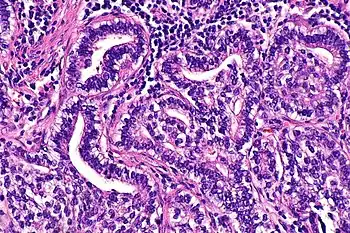

| Micrograph showing fetal adenocarcinoma. H&E stain. | |

FA is an epithelial tumor whose cells and architecture resemble that of fetal lung tissues in the pseudoglandular stage of development (which occurs at about 10–16 weeks gestation in the human),[6] with complex glandular structures and morules with cell nuclei that appear clear due to the accumulation of biotin.[15]